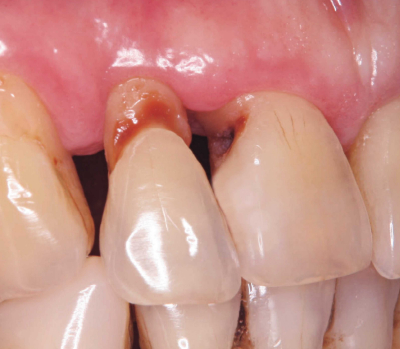

75歳の男性。上顎右側中切歯と側切歯の審美不良を主訴として来院した。6か月前から気付いていたが強い痛みがないのでそのままにしていたという。エアーで一過性の痛を認めるが、他に症状はない。検査の結果、修復処置を行うこととした。初診時の口腔内写真を別に示す。

適切な修復材料はどれか。2つ選べ。

a. コンポジットレジン

b. リン酸亜鉛セメント

c. グラスアイオノマーセメント

d. 酸化亜鉛ユージノールセメント

e. タンニン・フッ化物合剤配合ポリカルボキシレートセメント